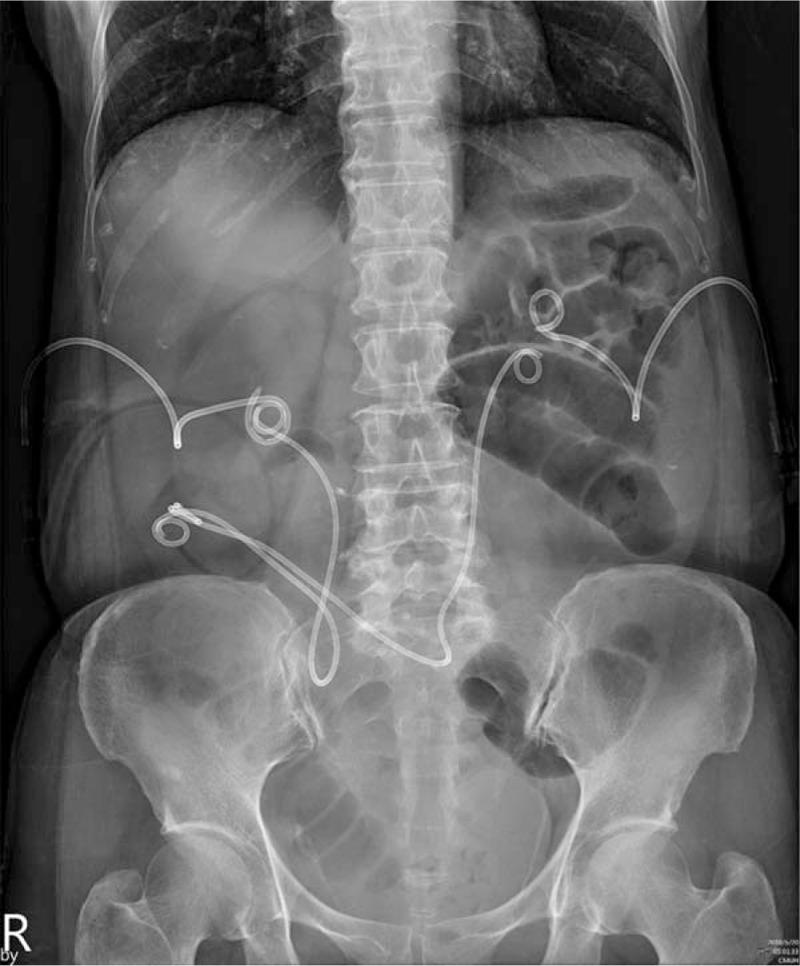

A 64-year-old woman presented with symptom of small bowel obstruction such as nausea, vomiting, and abdominal fullness after RARC and Indiana pouch. Another 61-year-old man presented with left obstructive hydronephrosis and recurrent pyelonephritis after RARC and ileal conduit.

Both patients received computed tomography scans and the results were suggestive of small bowel herniation between bilateral ureters and urinary diversion.

The 2 patients underwent open ureterolysis and internal hernia reduction. During the operation, bowel loop herniation between the interureteral spaces were found.

一名64岁女性在接受RARC及印第安纳袋手术后出现小肠梗阻症状,如恶心、呕吐和腹胀。另一名61岁男性在接受RARC及回肠代膀胱术后出现左肾梗阻性积水和复发性肾盂肾炎。

两名患者均接受了计算机断层扫描,结果提示双侧输尿管与尿流改道之间存在小肠疝。

两名患者均接受了开放性输尿管松解术及内疝复位术。术中发现输尿管间隙之间存在肠袢疝。